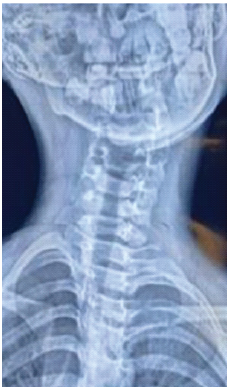

Chronic Irreducible C1–C2 Rotatory Subluxation Presenting as Painful Torticollis in a Child Managed with Posterior Lateral Mass Fixation: A Case Report

Sachlang Debbarma , Chirag Sharma , Ajoy Baishya , Tashi G Khonglah , Bhaskar Borgohain , Sharat Agarwal